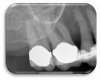

Figure 1. High-resolution, focused field-of-view CBCT scan of the posterior left mandible.

Figure 1

Every patient is unique, and every clinical situation requires a treatment plan customized to meet each patient's needs. In the same way, CBCT imaging can and should be customized to each patient or diagnostic task to optimize image quality and increase diagnostic accuracy. It can be easy to "set it, forget it" and take the same scan on every patient who needs a scan, but tailoring the settings on a CBCT machine can significantly affect image quality and increase diagnostic accuracy (Figure 1 and Figure 2). Some of the configurable factors include field of view, voxel size, patient positioning, and metal artifact reduction (MAR) reconstruction algorithm.